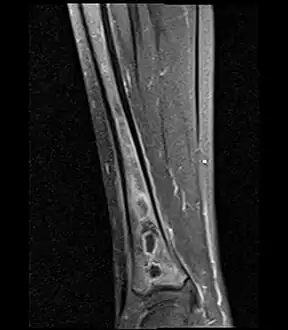

Fat saturated STIR (short tau inversion recovery) image showing hyperintense edema in the calf musculature, marrow edema, and subperiosteal pus. The intramedullary abscess cavity is hyperintense as well. -

Coronal fat suppressed STIR image showing, bone marrow and subcutaneous edema as well as subperiosteal edema. The thin hypointense rim surrounding the intramedullary collection represents the reactive interface between the abscess and the body's attempt to wall it off. -

Sagittal T1-weighted fat-suppressed post gadolinium image showing the extent of the multiloculated intramedullary abscess.